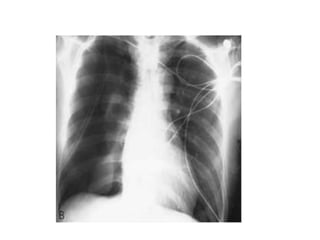

Barotrauma pneumothorax

• Defined as that occurring in a patient receiving positive-pressure

ventilation.

• Often attributed to areas of the lung that become overdistended

during mechanical ventilation as other areas are consolidated and

poorly ventilated.

• As a general rule, any barotrauma pneumothorax is an indication

for tube thoracostomy